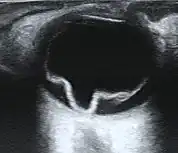

| Cross section of retinal detachment | |